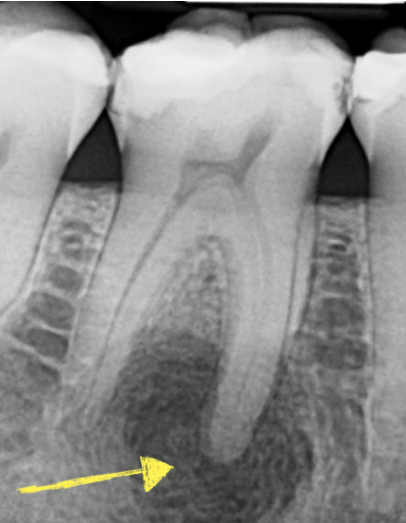

Tooth Trauma

Patient: Karen S., 44